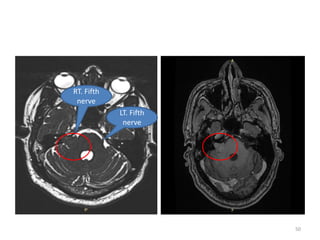

• PRESENTATION • 59 year male

• Diagnosed case of vestibular schwannoma

• Right side

• P/w Slight decreasing in hearing loss-4 - 5 months

• MRI • Intracanalicular and extra canalicular component

• Impending 5th nerve

• SRS • SRS

• 25Gy/5#

LT. Fifth

nerve

RT. Fifth

• NAME • UMR •PRESENTATION • 59 year male • Diagnosed case of vestibular schwannoma • Right side • P/w Slight decreasing in hearing loss-4 - 5 months • No facial numbness • MRI • Intracanalicular and extra canalicular component • Touching brainstem • No cystic component • Minimal enhancing • Impending 5th nerve • SRS • SRS • 25Gy/5# Case details 49